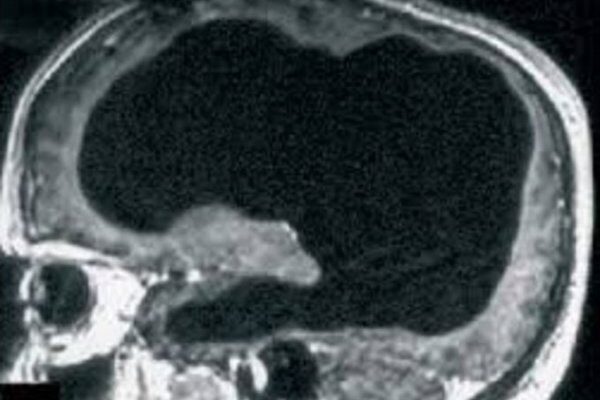

Các bác sĩ đã sửng sốt khi nhìn thấy 90% não bộ của một người đàn ông Pháp biến mất mà người này vẫn sống khỏe mạnh và sinh hoạt bình thường.

Mặc dù bị tổn thương tới 90% bộ não, một người đàn ông Pháp vẫn có thể sống và hoạt động bình thường, điều này đã thách thức sự hiểu biết của các nhà khoa học.

Sau khi tiến hành chụp X-quang não, các bác sĩ đã vô cùng kinh ngạc khi thấy phần lớn não bộ của người đàn ông này đã dần dần bị phá hủy trong suốt 30 năm qua bởi sự tích tụ của các chất lỏng trong não, tình trạng này được gọi là não úng thủy.

Mặc dù mô não chỉ còn lại một khoảng nhỏ, tinh thần và mọi hoạt động của người đàn ông này không bị ảnh hưởng. Chỉ số IQ của ông chỉ dừng ở con số 75 điểm, nhưng ông vẫn rất minh mẫn và luôn hoàn thành tốt công việc công chức của mình. Hiện tại ông đã kết hôn và có 2 con, sức khỏe của ông tương đối khỏe mạnh.